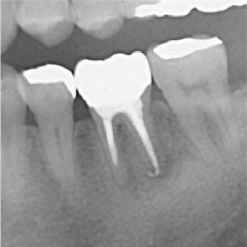

当院で処置した症例をご紹介します。

他院で抜歯と言われてしまった歯でも抜歯せずに対処した症例も多数あります。

黒い影が出ている部分が問題の個所で(根尖病巣)、治療後はこの影がなくなっているのが見て取れると思います。

保険適用。根尖病巣を治療した症例。リスクとして、稀ではありますが再発することがあります。